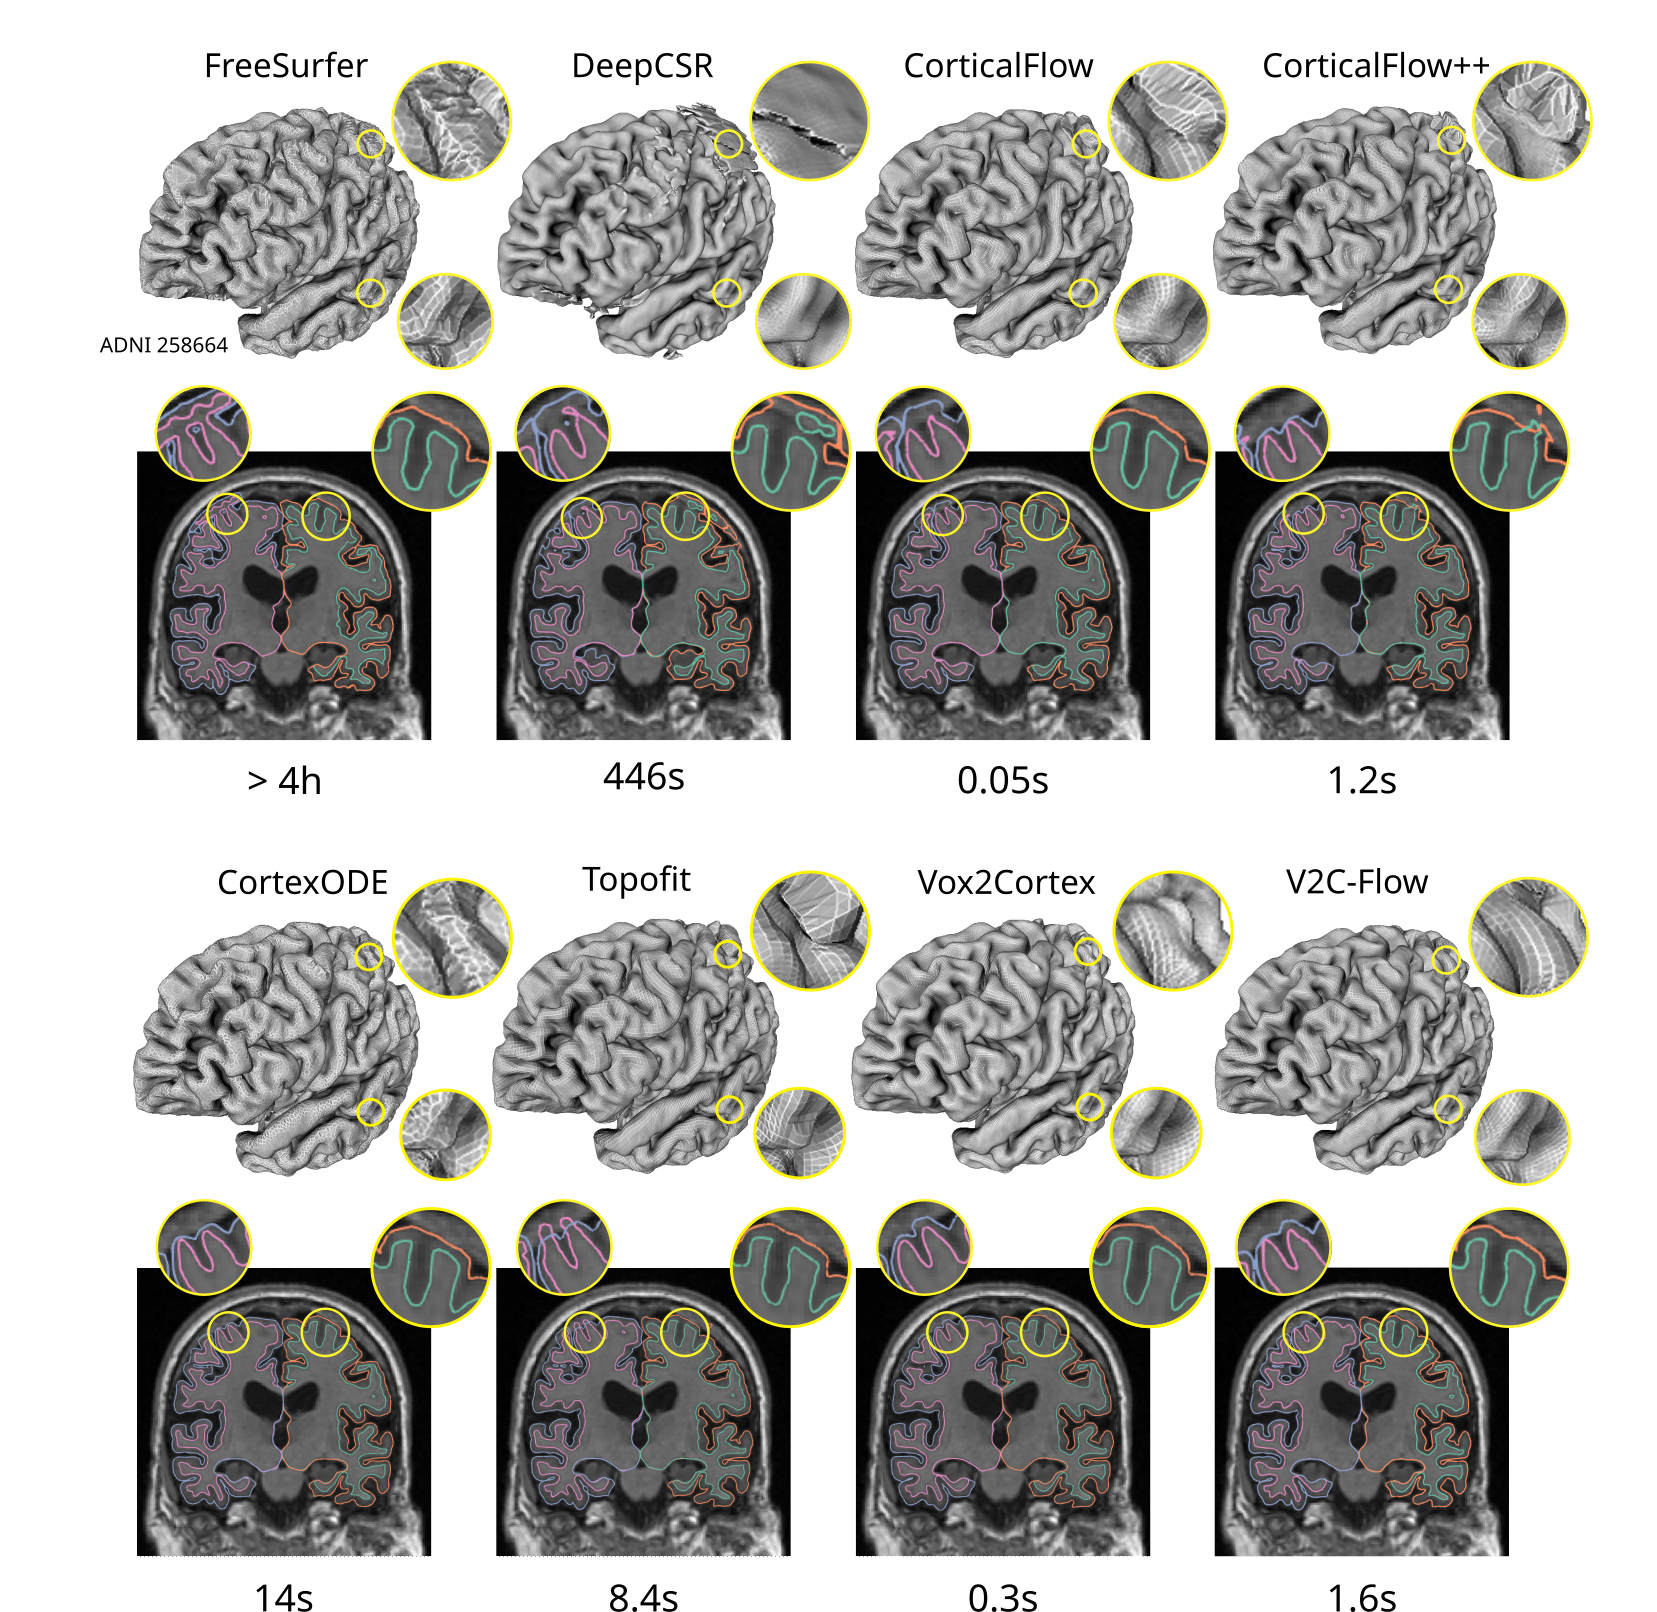

An important aspect of cortical surfaces is the obtained accuracy since cortical folds are often tighter than the typical scan resolution of 1mm per voxel. We evaluate the accuracy of V2C-Flow and compare it to recent state-of-the-art cortex reconstruction methods using the ADNI data. Quantitatively, we evaluate the accuracy of all methods with respect to the FreeSurfer [9] (v7.2) silver standard in Table 1. We compute the average symmetric surface distance (ASSD) and 90-percentile Hausdorff distance (HD90) from 100,000 randomly sampled surface points (see Supplementary Material for details).

In comparison to other DL-based methods for cortical surface reconstruction, V2C-Flow performs comparable to the best alternative methods, i.e., CorticalFlow++ (CF++) and CortexODE (CODE), with V2C-Flow being in the forefront on both, WM and pial, surfaces. We attribute the highest accuracy of CF++, CODE, and V2C-Flow to the continuous-time deformation process that they have in common. In terms of training time, though, V2C-Flow is about 10 times faster than CF++, taking three days instead of four weeks. The long training time in CF++ is probably due to the compute-intensive ODE-solver (Runge-Kutta method with 30 integration steps) and the separate modeling of the deformation fields (three UNets per surface). CODE, on the other hand, is slower in terms of inference time (14s vs. 1.6s in V2C-Flow, cf. fig. 3) due to the sequential segmentation and mesh extraction approach and does not come with point correspondences to a template. Other DL-based baseline methods, either template-based (Vox2Cortex [2] (V2C), CorticalFlow [29] (CF), TopoFit [21]) or SDF-based (DeepCSR [50]), are clearly outperformed in terms of surface accuracy. Supported by the observations from Figure 3 and Supplementary Table 2, we further argue that the separate modeling of surfaces in CF/CF++ and TopoFit bears the risk of creating many anatomically implausible intersections between WM and pial surfaces. Instead, the joint modeling in V2C-Flow reduces the number of intersecting WM and pial surfaces. Further artifacts of existing methods like intersections with the skull (CF, CF++) and distorted surfaces (DeepCSR, FreeSurfer) are also alleviated in V2C-Flow as shown in Figure 3.

In terms of inference time, all deep learning-based methods offer a drastic speedup from several hours to seconds compared to traditional CPU-based frameworks like FreeSurfer. This is mainly due to the parallel processing on GPUs. Yet, the topology correction and surface extraction routine in DeepCSR and CortexODE requires a couple of seconds or minutes, depending on the implementation. Template-based methods (TopoFit, CF, CF++, V2C, V2C-Flow) are the fastest as they do not require topology correction and surface extraction; they directly yield usable cortex meshes.

Refer to caption

Fig. 3: V2C-Flow yields accurate and smooth surfaces while alternative methods introduce artifacts in this sample from the ADNI test set. The required inference time is measured in seconds (s) or hours (h) for the reconstruction of the four cortical surfaces of one subject on an Nvidia A6000 GPU for DL-based methods and on a single CPU for FreeSurfer (v7.2).